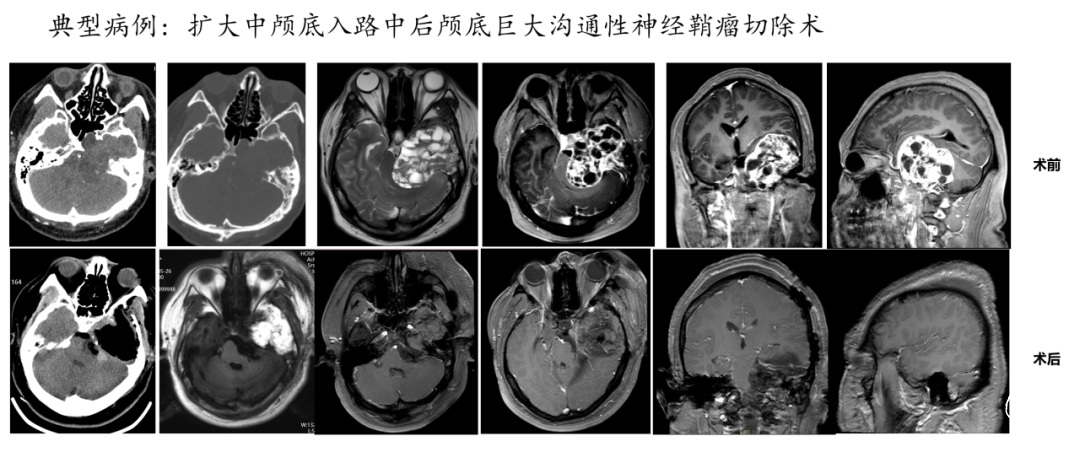

复杂脑肿瘤及颅内外沟通性肿瘤的手术治疗是神经外科领域的一项具有挑战性的任务,这些肿瘤往往因其位置特殊、结构复杂、与周围组织(血管及神经)关系密切而增加了手术的难度,需要医生具备高超的手术技巧和丰富的临床经验,也常需要多学科团队的协作。我们科室常与耳鼻喉科、口腔颌面外科、头颈外科、肿瘤科等协同合作,能实现最大范围的安全切除,确保患者得到全面的治疗和护理。